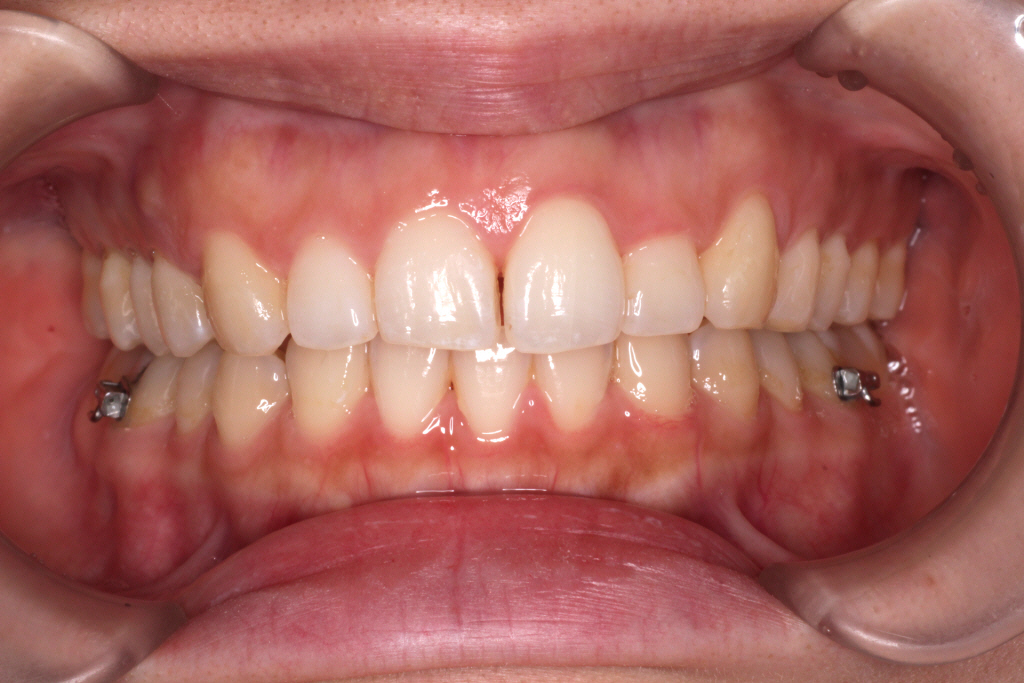

こちらがカリエールモーション終了時の口腔内写真です。

正中のずれが治ってきているのと、

上の前歯のがたつきが少しよくなっているのが分かります。

また、右の奥歯が1歯分後ろにさがっている事が分かります。

この状態まできたら、カリエールモーションの装置をはずし

今度はインビザラインにて治療を行っていきます。